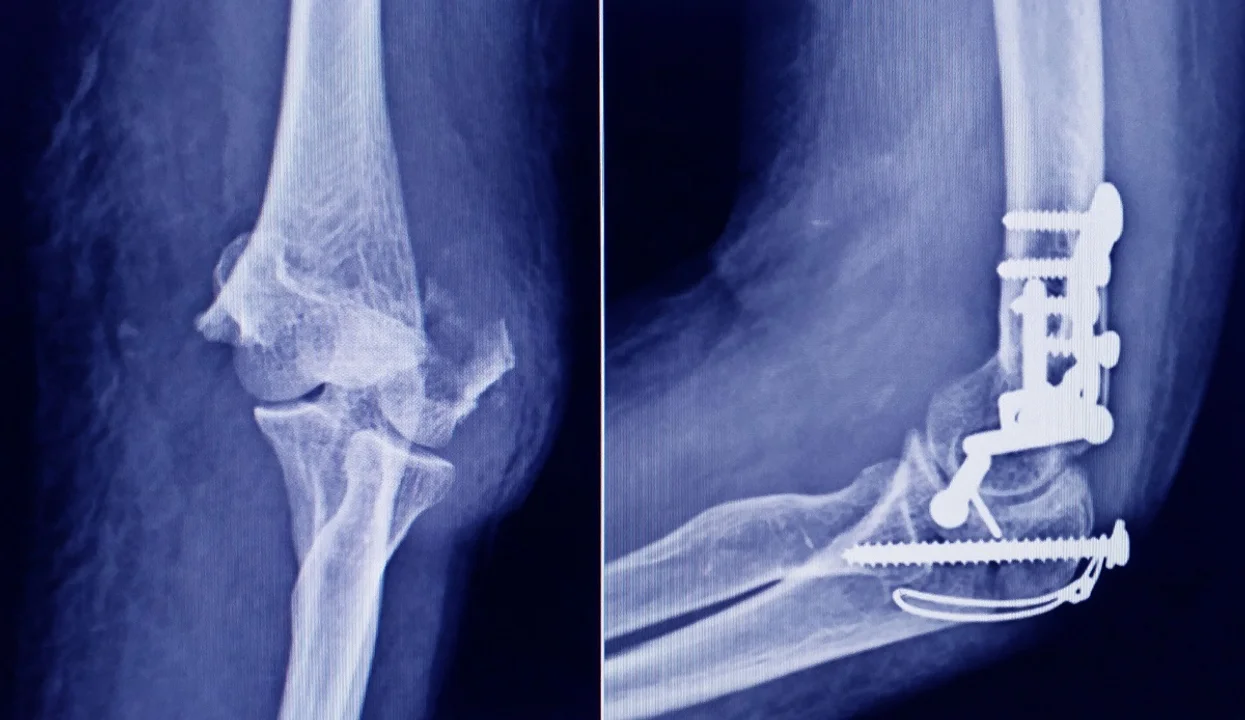

La Administración Nacional de Medicamentos, Alimentos y Tecnología Médica (ANMAT) advirtió a la población por un tornillo utilizado en cirugías traumatológicas debido a que es falso, por lo que su uso representa riesgo para la salud del paciente al que se lo implante.

Se trata de un tornillo utilizado en cirugías traumatológicas que fue detectado durante una inspección de control de mercado realizada en una ortopedia ubicada en la ciudad de San Miguel de Tucumán.

Las autoridades de la ANMAT dieron a conocer las características del producto para su advertencia: STRYKER 10 mm X 28 mm – BIOABSORBABLE – ACL INTERFERENCE SCREW – REF 234-010-067 – LOT 90905.